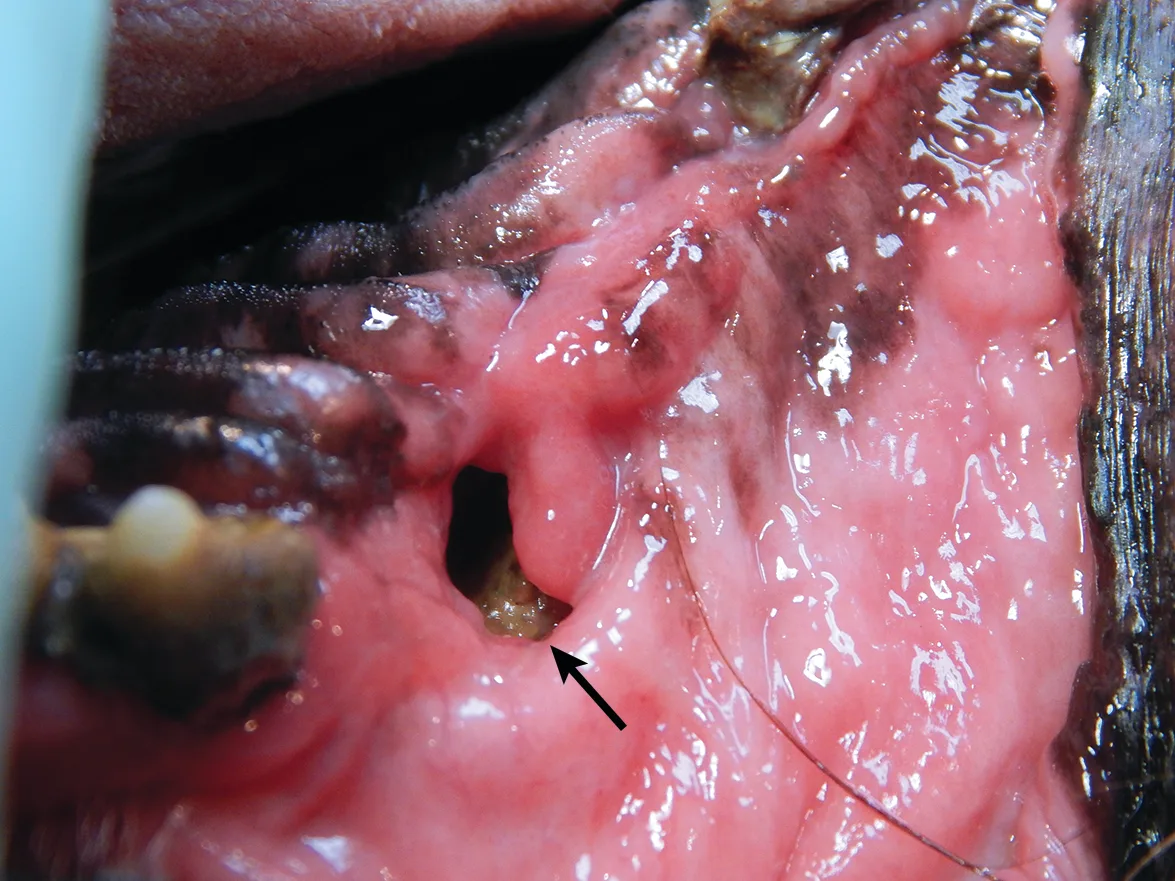

Oronasal fistulas may often be present prior to surgical extraction of maxillary teeth (Figures 6 and 7) but can also be a result of the surgical procedure. Although any maxillary tooth extraction can result in an oronasal fistula, it is most common following extraction of a maxillary canine tooth. Inadequate healing may lead to chronic oronasal fistulation (Figure 8). The quality of the tissue used to close the fistula and lack of wound tension are especially important in closure of oronasal fistulas. Development of a healthy recipient bed for the flap (Figure 9) and use of an Elizabethan collar to prevent self-trauma by the patient can also reduce flap failure.4

A chronic oronasal fistula (arrow) at the extraction site of the right maxillary canine tooth. Foreign material can be seen in the nasal cavity.